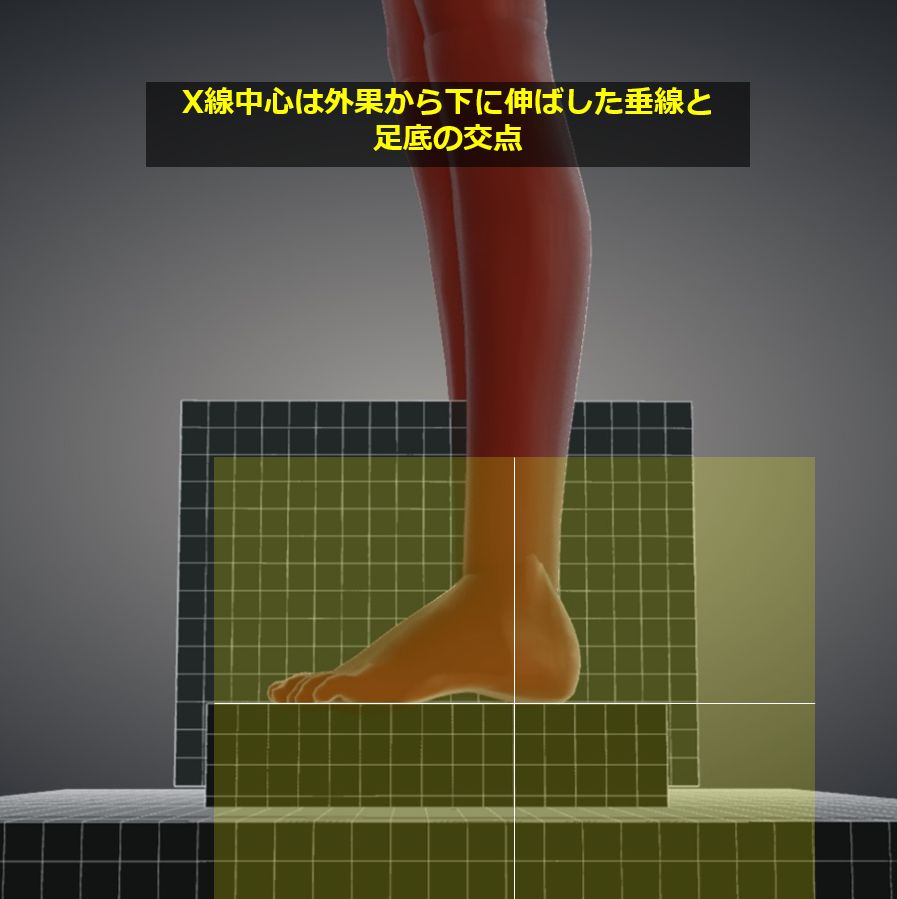

椎体、顔面、頭部の単純撮影法 | 診療放射線技師国家試験 対策ノート。椎体、顔面、頭部の単純撮影法 | 診療放射線技師国家試験 対策ノート。椎体、顔面、頭部の単純撮影法 | 診療放射線技師国家試験 対策ノート。折れや擦れはあります。。足部側面撮影 (立位荷重撮影), Foot lateral view (weight。気になる方はご遠慮ください。歯科矯正メカニクス -その普遍性と臨床応用- Ⅱ